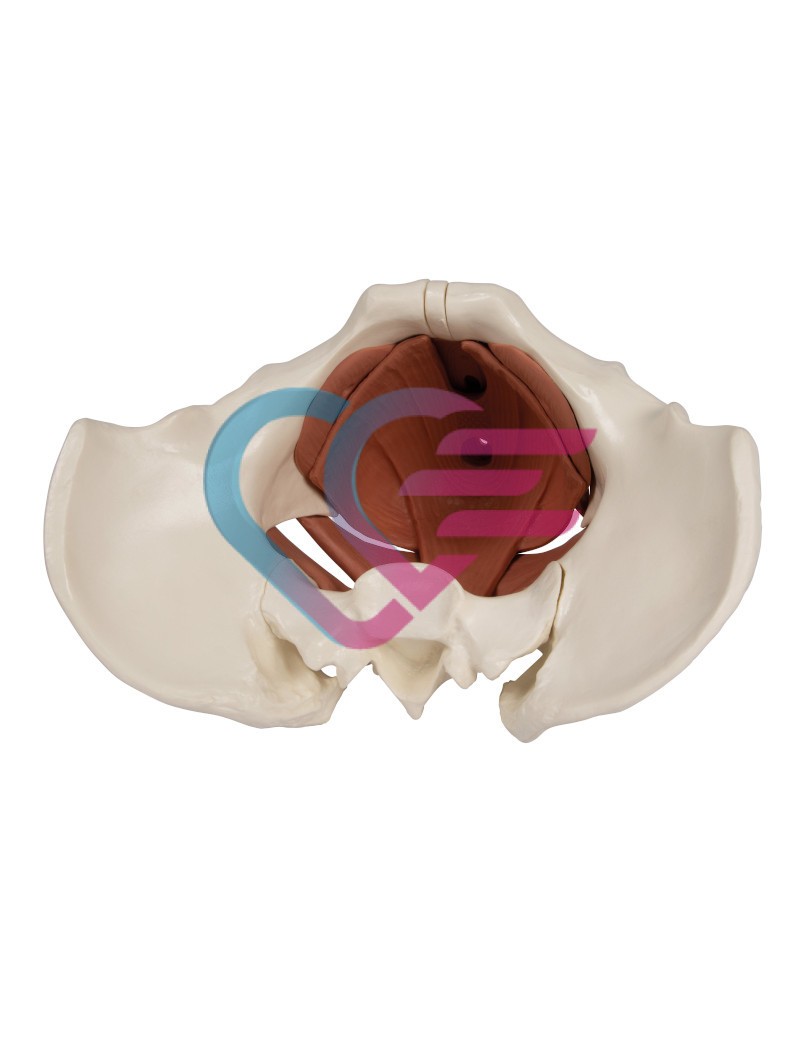

- Poboljšani model dna ženske zdjelice predstavlja zdjelično dno u njegovim slojevima.

- Sastoji se od 12 dijelova.

- Sadrži također 2 kosti kuka i križnu kost.

- Mišići su povezani magnetima što omogućuje njihovo jednostavno uklanjanje radi demonstracije slojeva.

- Prikazani su sljedeći mišići koji se mogu ukloniti:

– diaphragma pelvis

– urogenitalna dijafragma

– sfinkteri urogenitalnog i digestivnog trakta.